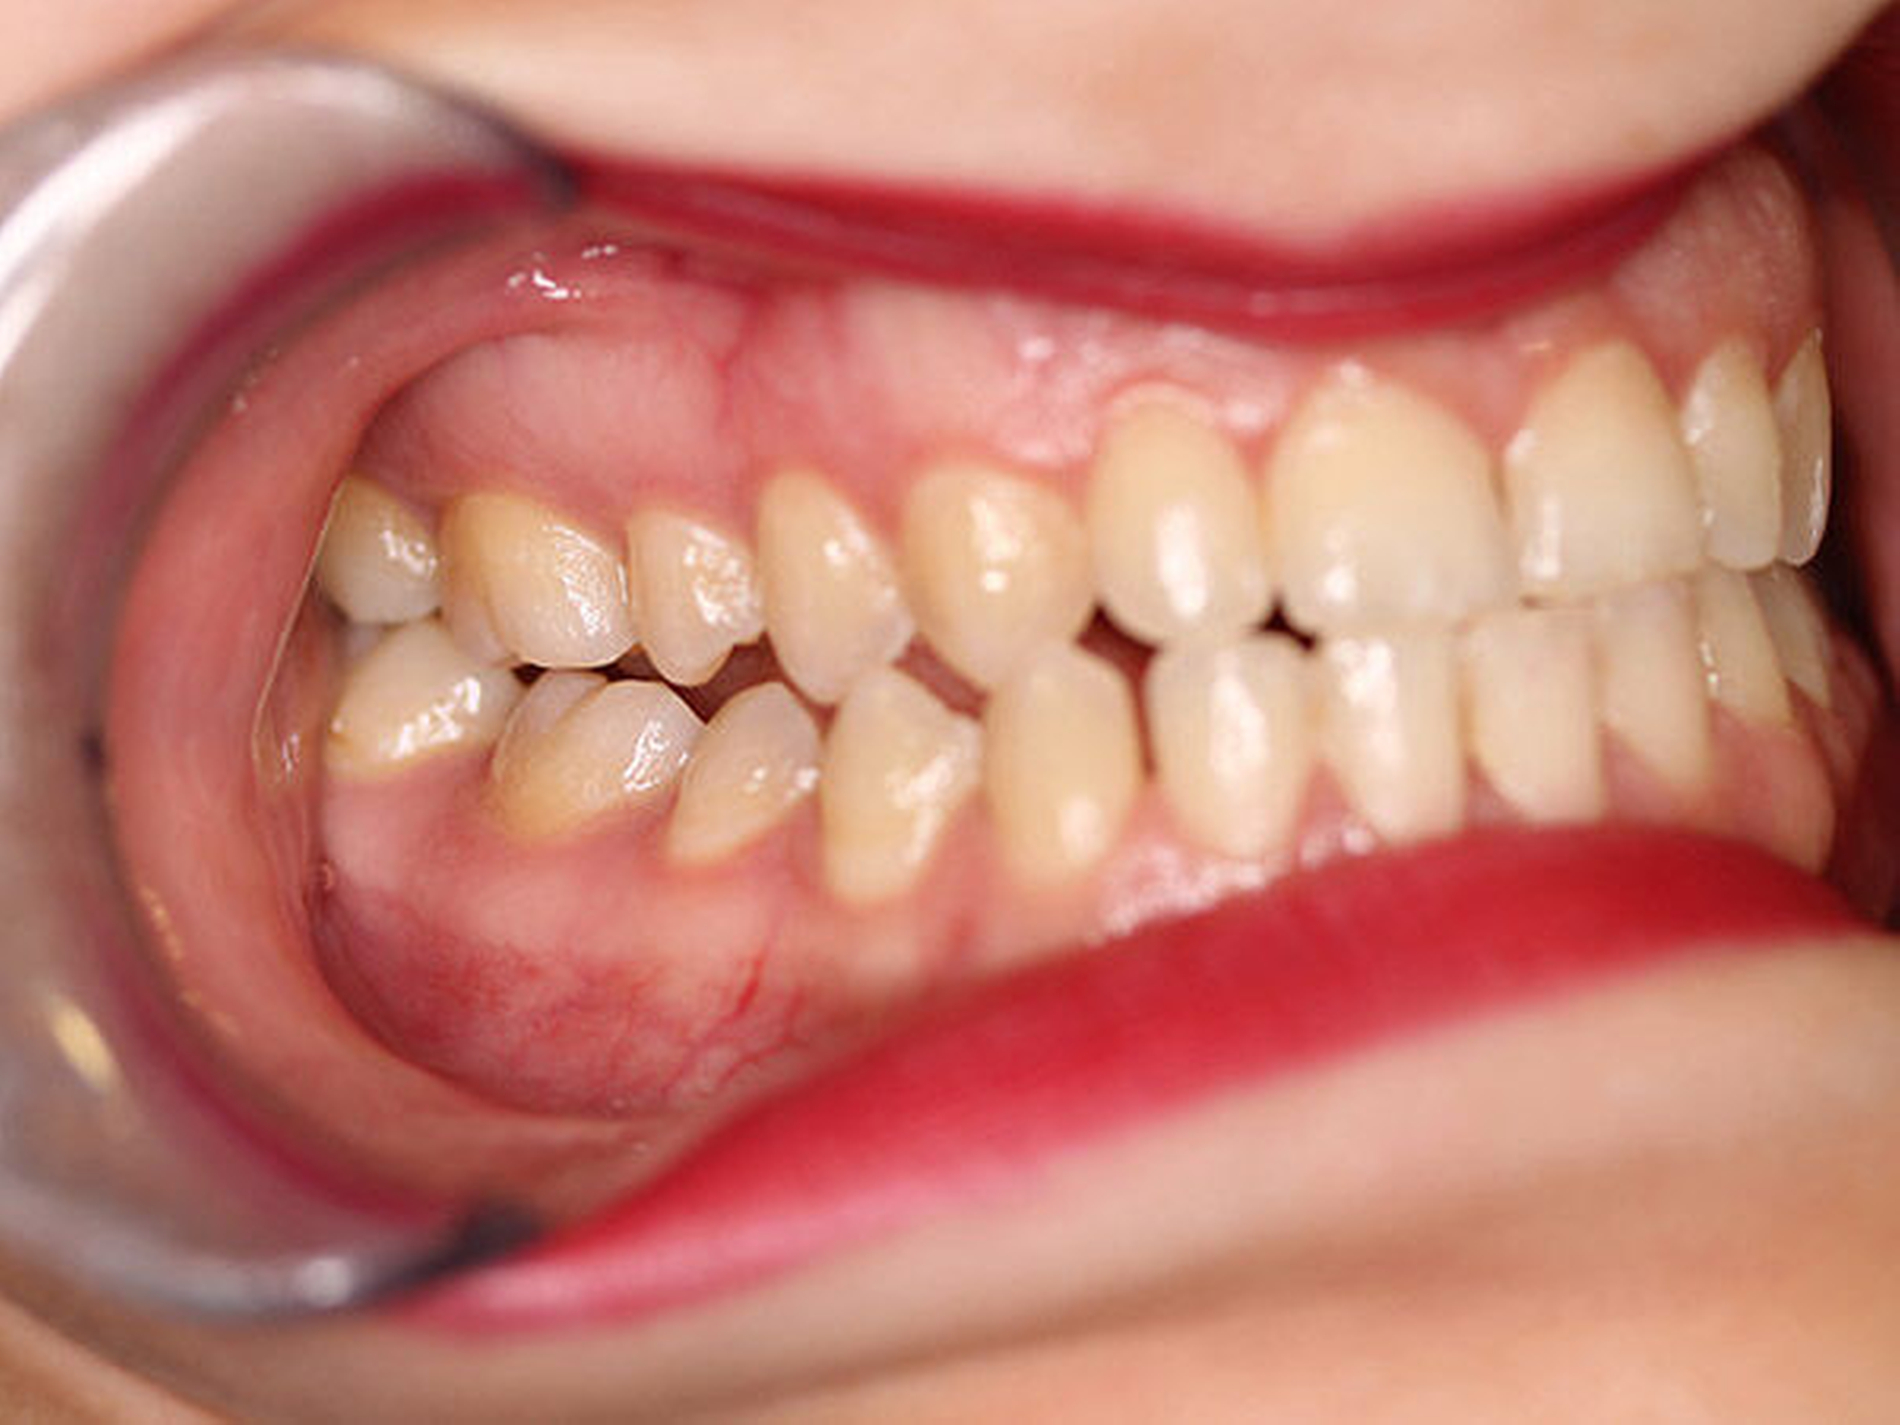

Intraoral fand sich eine Mesialbisslage von einer halben Prämolarenbreite im Seitenzahnbereich beidseits. Ein Kontakt bestand regio 16/47 mit Nonokklusion der restlichen ipsilateralen Eck- und Seitenzahnregion (Abbildung 2). In regio 11/41 fand sich eine Kreuzbisssituation, in regio 21/31 eine Kopfbisssituation. Die Unterkiefermittellinie war interessanterweise um 3 bis 4 mm nach rechts verschoben, das knöcherne Kinn hingegen nach links. Weitere faziale Fehlbildungen lagen nicht vor.